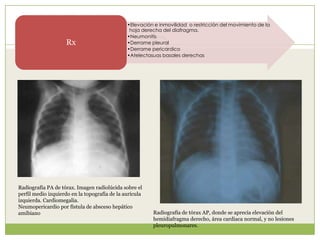

•Elevación e inmovilidad o restricción del movimiento de la

hoja derecha del diafragma.

•Neumonitis

•Derrame pleural

•Derrame pericardico

•Atelectasuas basales derechas

Rx

Radiografía de tórax AP, donde se aprecia elevación del

hemidiafragma derecho, área cardiaca normal, y no lesiones

pleuropulmonares.

Radiografía PA de tórax. Imagen radiolúcida sobre el

perfil medio izquierdo en la topografía de la aurícula

izquierda. Cardiomegalia.

Neumopericardio por fístula de absceso hepático

amibiano